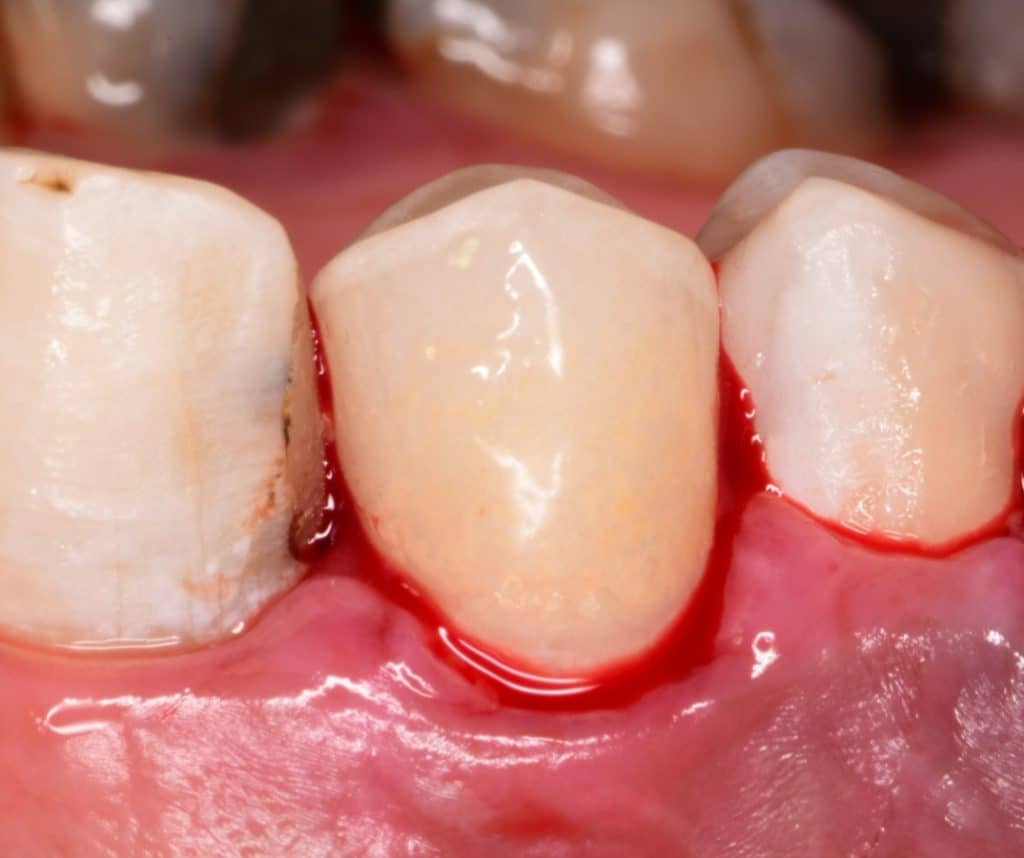

2 weeks later

2 weeks later, you can see the beauty of the restoration, the uniform colour 😍 and the healthy gingiva